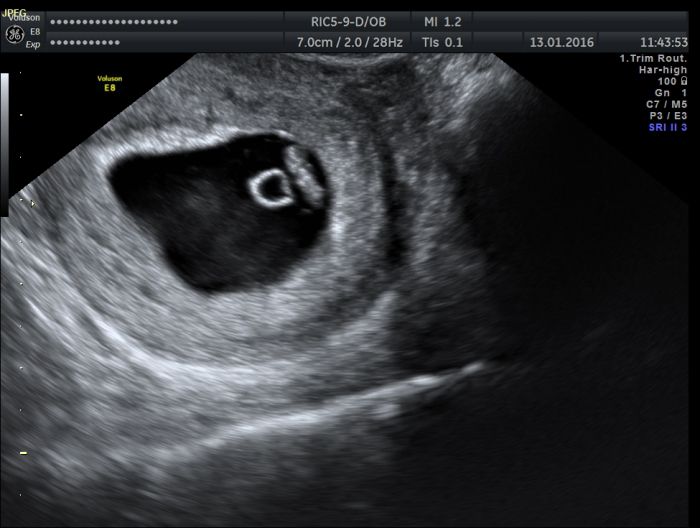

[848996] Já tam poznám jen ten váček, v ostatním se nevyznám Embarassed Prcek měl ke konci 7.tt 7,6mm a byla tam taková tyčinka

Lexi, mela jsem ted v polovine 7tt hodne podobny obrazek (ja jsem si o neho zapomela rict). Anamor, nechci nijak strasit, ale prijde mi to strasne malinky. Ja jsem mela posledni MS 20.12.a vcera na utz by bylo stejne velky, jak u Lexine.